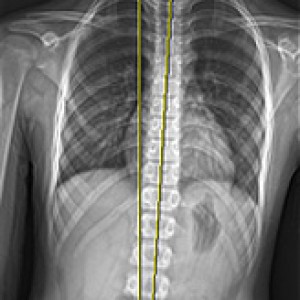

검사부터 다른 당당

“당당은 뼈만 보지 않습니다.”

근육과 근막의 정렬을 함께 진단하며, 풀 스파인 촬영을 통해 머리부터 모든 고관절, 발의 정렬까지 함께 파악하여 개개인에 맞는 전신 치료법을 설계합니다.

전신 엑스레이 검사

Before & After

해당 사진은 수정없는 실제 치료사진입니다.

환자의 치료결과는 환자의 상태, 치료방법 등에 따라 차이가 발생할 수 있습니다.